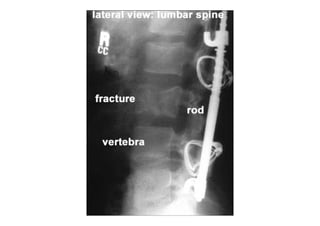

RADIOLOGIA DO

TRAUMA DO ESQUELETO

Referência: http://www.accessexcellence.org/RC/VL/